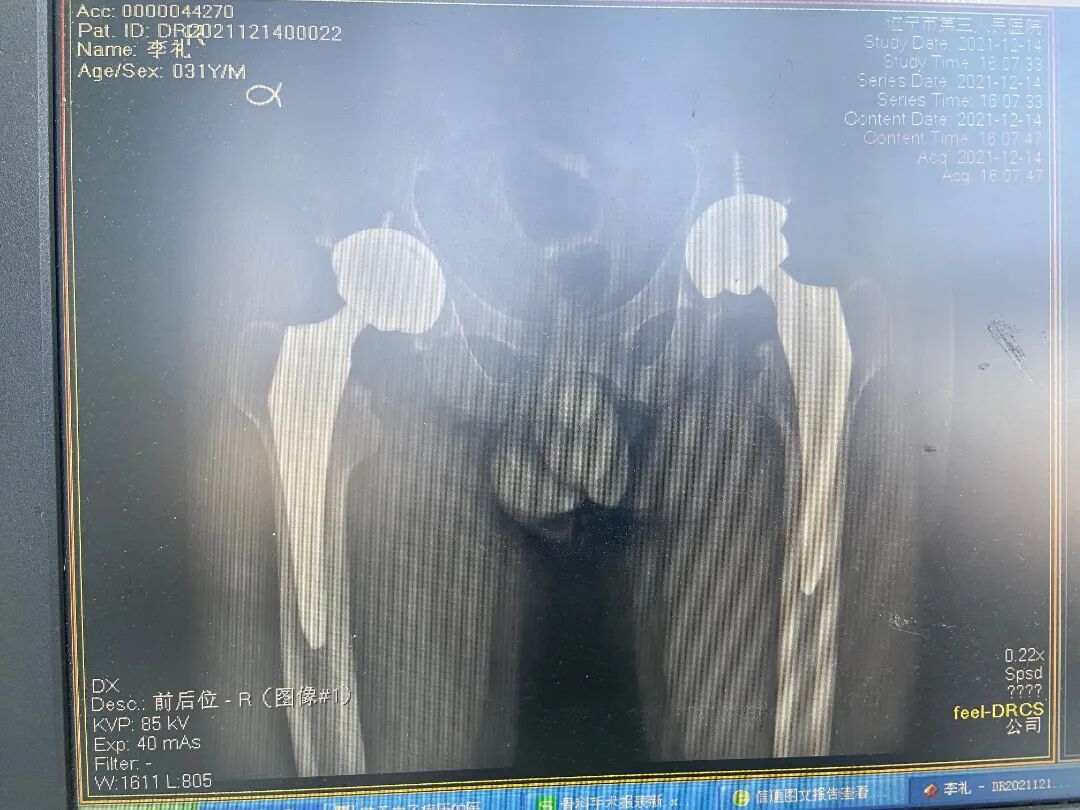

双侧股骨头坏死

双侧人工全髋关节置换术